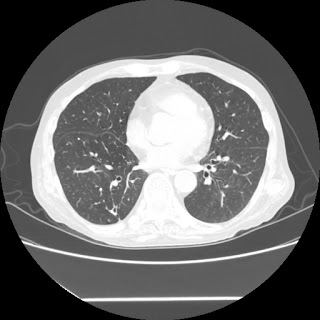

HRCT done on 17Mar16